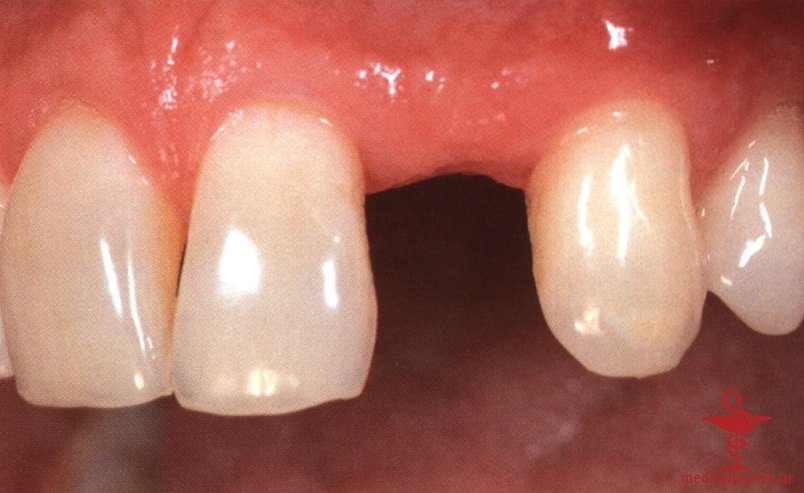

В частности, в эстетически значимой зоне имплантат не следует устанавливать в положении и направлении корня замещаемого зуба, поскольку в большинстве случаев это приведет к слишком вестибулярному положению и избыточному вестибулярному наклону имплантата. Обычно такая ситуация ассоциируется с выраженной рецессией десны, как это описывалось в отдельной статье на сайте (просим Вас пользоваться формой поиска по сайту выше) (рис. 1).